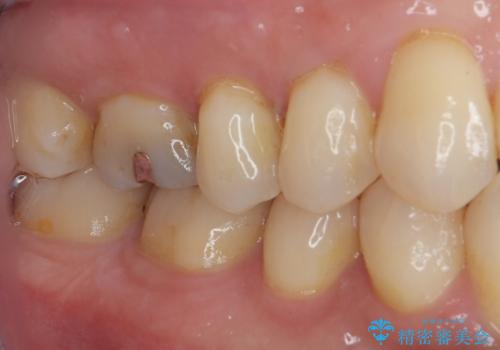

シリコーン印象材にて型どりをしました。

ゴールドは柔軟性があり、精密に加工できるため、歯とインレーのすき間が限りなく少ない状態で作成できます。これにより、虫歯の再発リスクを抑えることができます。